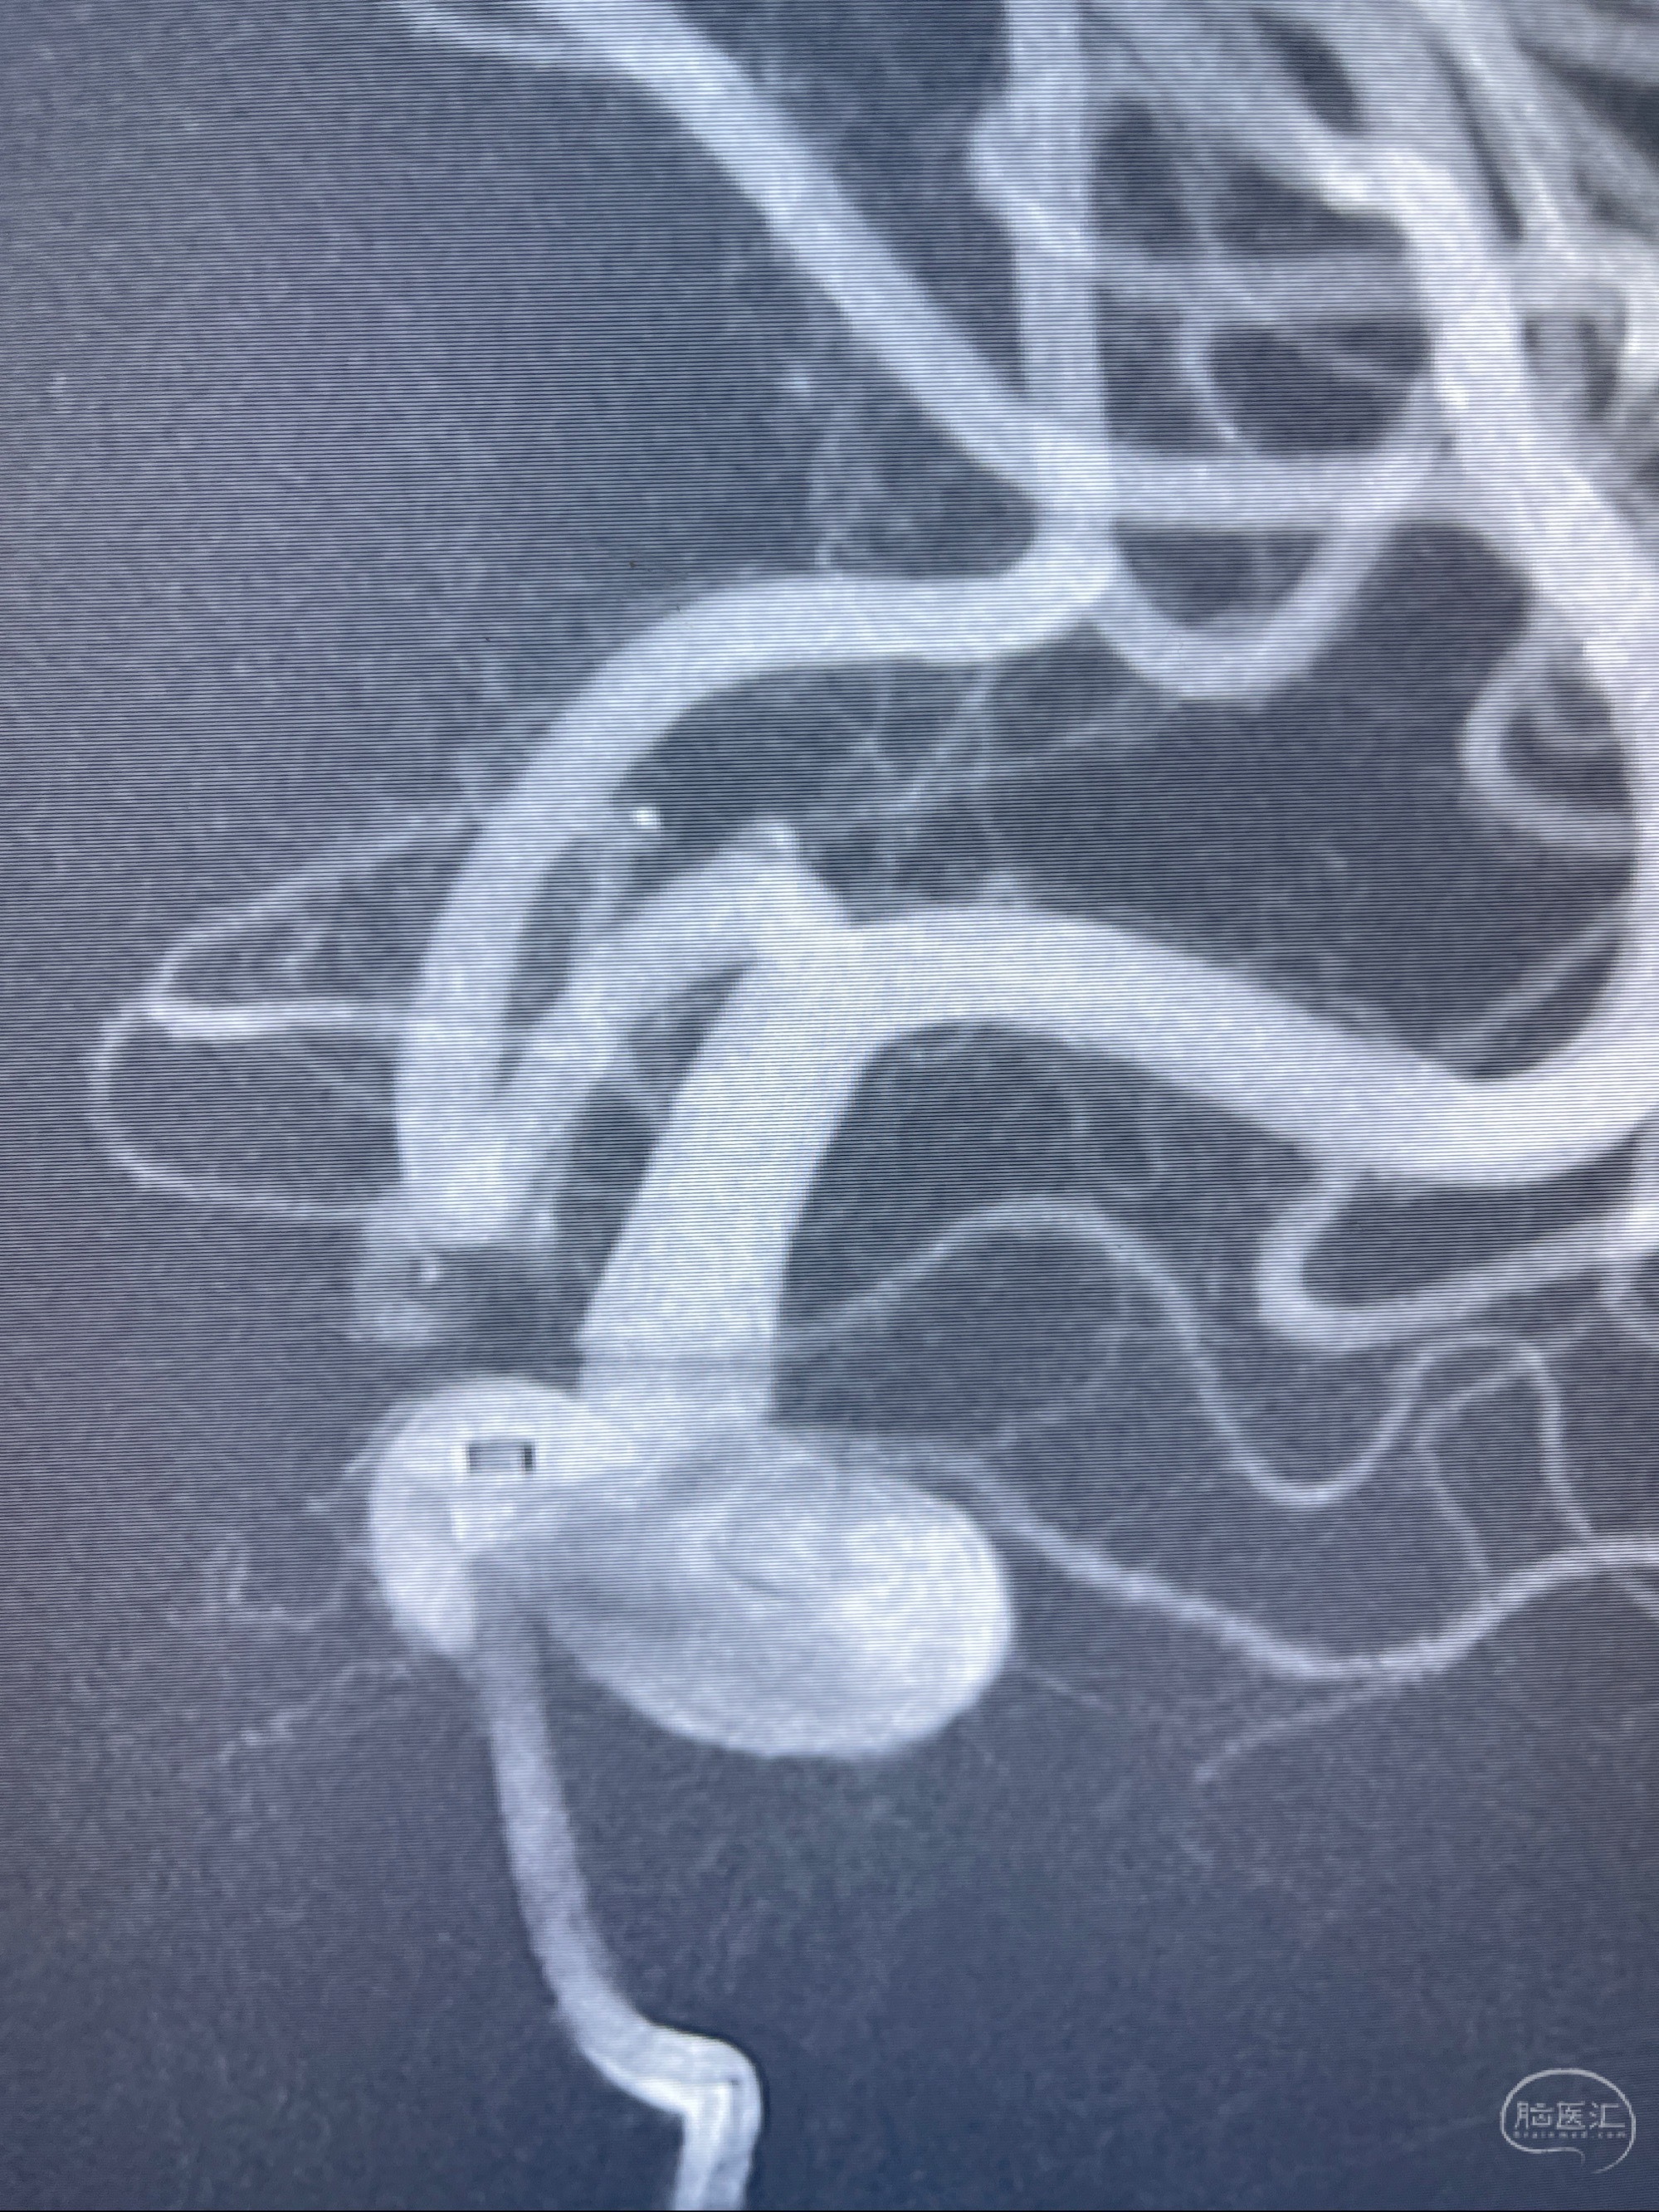

2023-07-27全脑血管造影:双侧颈内动脉眼动脉段动脉瘤,右侧较大

2023-08-01全麻下行双侧颈眼动脉瘤支架辅助栓塞

- pipeling4.5-20mm

- pipeline 4.0-20mm